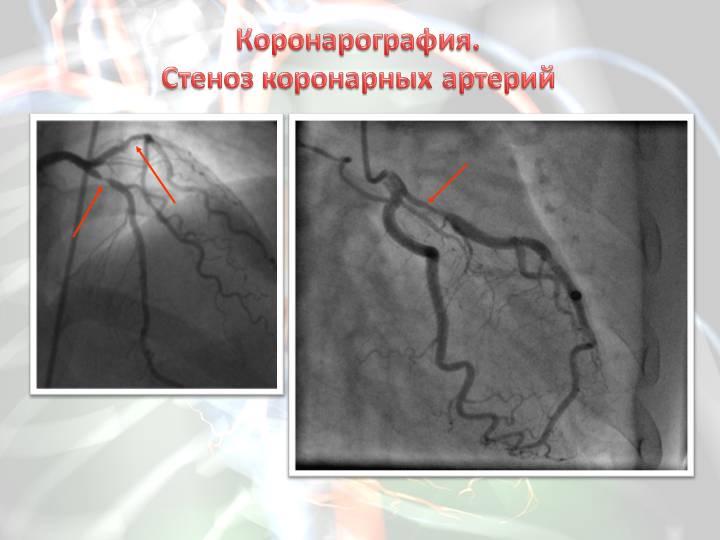

Анатомия коронарных артерий: КТ-изображения